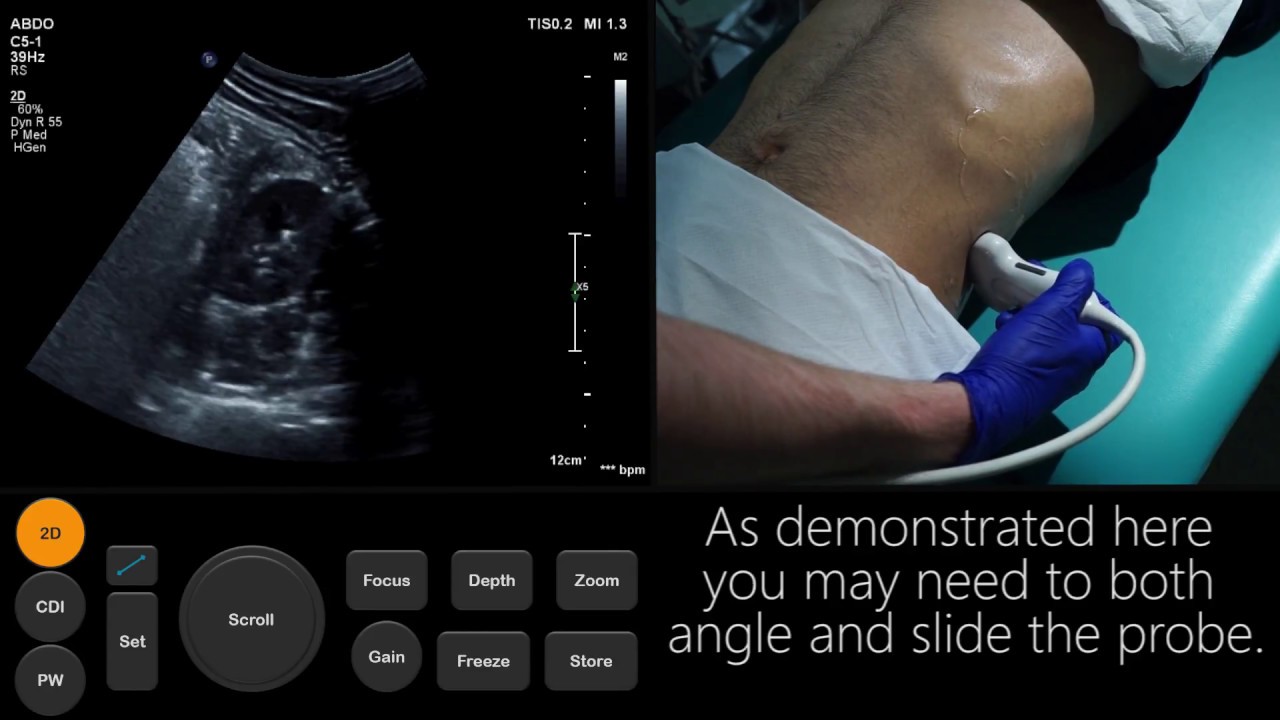

However, there are a few exceptions: A transducer is placed on the abdomen using the conductive gel. A sonohysterogram looks for and can detect uterine shape and congenital uterine abnormalities (like uterine septum, which is when tissue divides the uterus),.

Pelvic ultrasound may be performed using one or both of 2 methods: A transvaginal ultrasound is a relatively quick, painless imaging procedure that provides a more detailed view of. For some scans, such as a gallbladder ultrasound, your care provider may.

The following lists of tips and questions address basic ultrasound preparation. Most ultrasound exams require no preparation. Empty your bladder 90 minutes before exam time, then consume one 8.